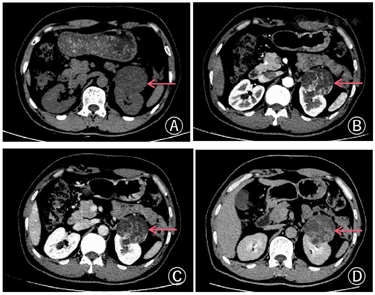

CT:CT示左肾可见一类圆形多房囊性混杂密度肿块,大小约53mm×46mm,边缘清楚,局部突出肾轮廓外,增强扫描示肿块壁和分隔不均匀增厚,动脉期实性部分呈结节状、条索状明显强化,囊性部分未见强化,门脉期实性部分密度低于肾实质,强化方式呈"快进快出"。(图1)

增强CT是目前术前诊断肾癌最常用的影像学方法。Xp11.2易位性肾癌在CT平扫中可表现为实性、囊性、囊实性结节,混杂密度,部分具有出血坏死、钙化灶等[7]。增强CT显示肿瘤强化明显,在皮质期和髓质期强化低于肾皮质,高于肾髓质,在延迟期强化低于肾皮质和肾髓质,肿瘤边界一般比较清楚[8],呈现较为典型的"快进快出"。文献报道Xp11.2易位性肾癌的CT表现与其他类型的肾癌轻微差别,如此肿瘤的CT增强幅度小于肾透明细胞癌[7],肿瘤平均直径比Ⅰ型乳头状肾细胞癌更大,包含更多的囊性成分[9]。本例病例中肾癌的CT表现为多房囊性混杂密度肿块,强化方式呈"快进快出",可以考虑诊断为肾癌,因其含有较多囊性结构,除考虑囊性肾癌外,还需要考虑Xp11.2易位性肾癌可能。